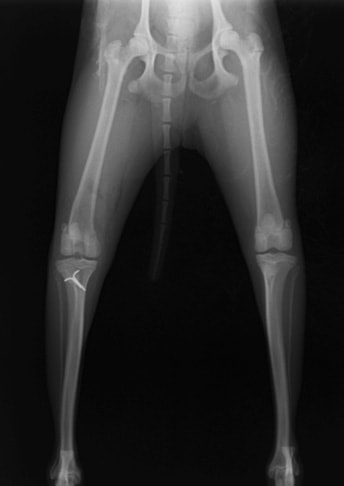

■ 症例22 ポメラニアン 1歳5か月 去勢雄

左後肢の挙上を主訴に来院した。整形学的検査、レントゲン検査より左右の膝蓋骨脱臼(左GradeⅡ〜Ⅲ、右Grade Ⅱ)を認めた。また、脛骨の前方引き出し試験の際に、引き出し兆候は認められないものの、疼痛が認められたため、前十字靭帯の損傷が疑われた。術中における、目視および関節内の操作によって、前十字靭帯の損傷や過伸展といった異常が認められなかったため、膝蓋骨脱臼の整復のみ実施した。手術手技は縫工筋及び内側広筋の解放、脛骨粗面の外側転位、滑車ブロック形造溝術、内外側関節包の縫縮を実施した。本症例は跛行もなく経過良好である。しかし、頸骨高平部の角度(TPA)が 右26.2°、左24.9°であり、解剖学的に前十字靭帯損傷のリスクが高いことから今後の経過に注意が必要である。